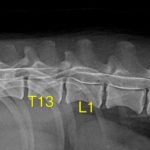

ダックスさんが腰を抜かして歩けなくなっているので早急に対応してほしいと主治医より連絡がありました。神経学的にグレード4の椎間板ヘルニアが確定されました。すぐさま脊髄造影検査とCTを行い、病変部を片側椎弓切除術により除圧術を行いました。術後にはリハビリテーションが計画されています。